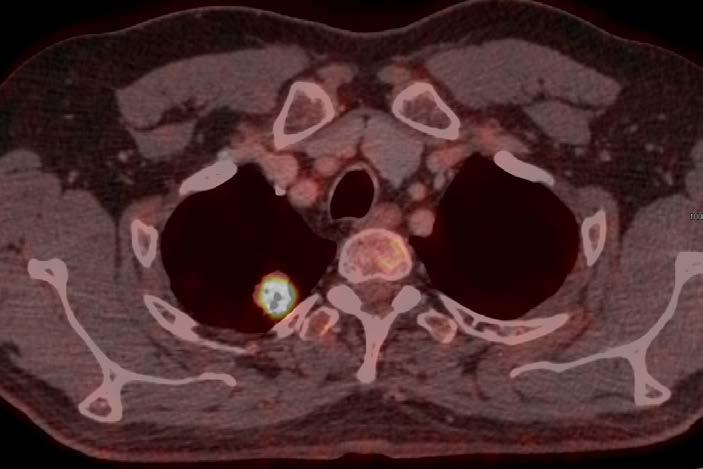

Mynd 6-1 Lítið lungnakrabbamein í hægra lunga (ör) sem fannst við skimun með tölvusneiðmyndum.

Með tilkomu tölvusneiðmyndatækni (TS) varð unnt að finna mun smærri hnúta í lungum en áður var mögulegt með hefðbundnum röntgenmyndum (mynd 6-1). Á síðustu áratugum hefur verið efnt til stórra framvirkra samstarfsverkefna, bæði í Bandaríkjunum og Evrópu. Fyrstu rannsóknir á skimun með TS voru gerðar í Japan og fyrsta alþjóðlega rannsóknin benti til þess að unnt væri að finna um